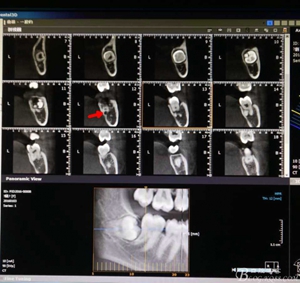

圖2.術(shù)前的cbct檢查:38牙冠周圍有骨組織覆蓋,下頜神經(jīng)管離38牙冠還有一定距離,在去除牙冠的時候,損傷神經(jīng) 的風險較小。38牙根舌側(cè)骨壁較薄。

圖3.冠向檢查:38牙根未進入下頜管內(nèi),牙冠周圍有牙囊影。

圖4.術(shù)前的CBCT縱剖面檢查:38牙根1/3緊鄰下頜管,看紅色箭頭。提示盡量不要斷根,如根尖折斷,取根導致下頜神經(jīng)損傷的風險加大